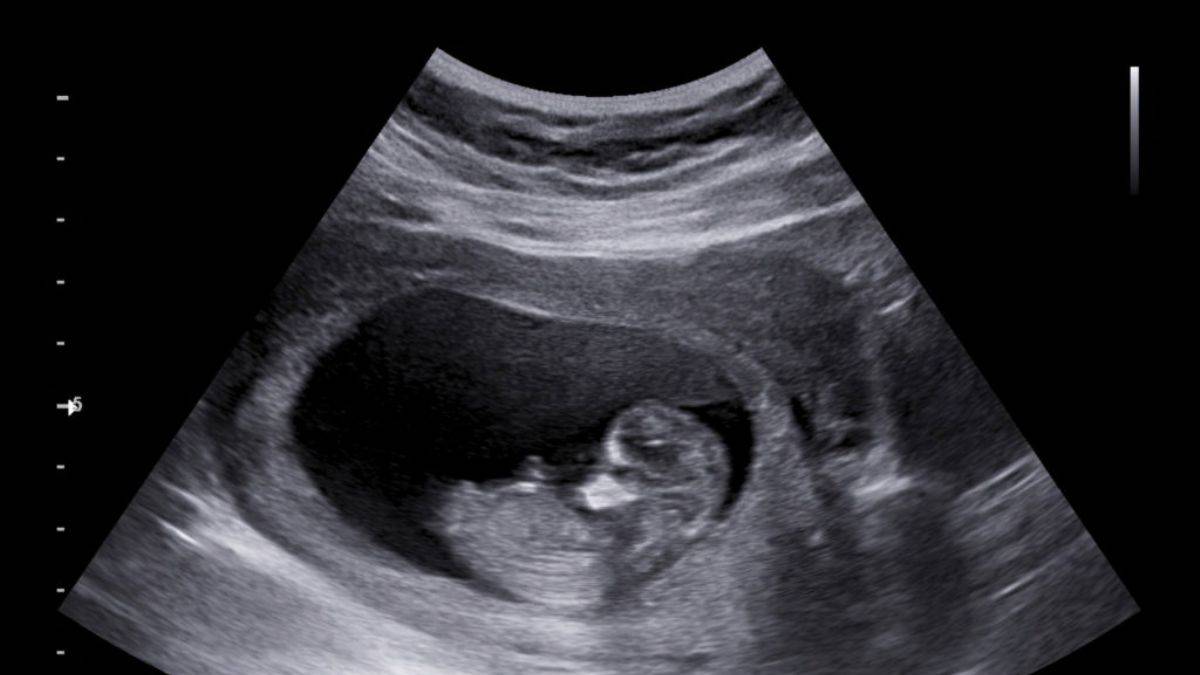

Şizofreni, anne karnındayken ortaya çıkıyor

Bilim insanları, şizofreniye neden olan hücrelerin erken gebelik döneminde henüz anne karnındaki bebeklerde görülebileceğini ortaya koydu.

Bulgular, şizofreni hücrelerinin her zaman kalıtsal olmadığını, kişinin henüz erken gebelik döneminde ya da gebelik komplikasyonları sonucu hastalığın gelişebileceği fikrini güçlendirerek erken teşhisi mümkün kılabileceğini gösterdi.

2017'de laboratuvarda geliştirilen hücre demetlerinin incelendiği araştırmada hızla bölünen ve farklılaşan düzensiz beyin hücrelerinin şizofreniye yol açabileceğine dair kanıtlar bulundu. 2021'de komplike hamileliklerde plasentada aktif olan ve şizofreniyle ilişkili bulunduğu belirlenen genlere rastlandı.